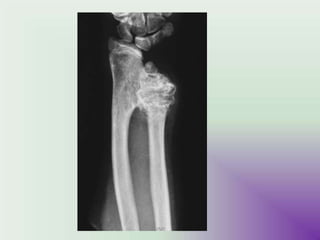

Radiographic features

• X ray

sharply defined, expansile

osteolytic lesions, with thin

sclerotic margins.

Eccentricity is typical.

But very often missed out due to

cortical thinning due to ballooning.

CT

Demonstrates these findings to a

greater degree, and is also better at

assessing cortical breach and

extension into soft tissues.

Fluid fluid levels (better than MRI)